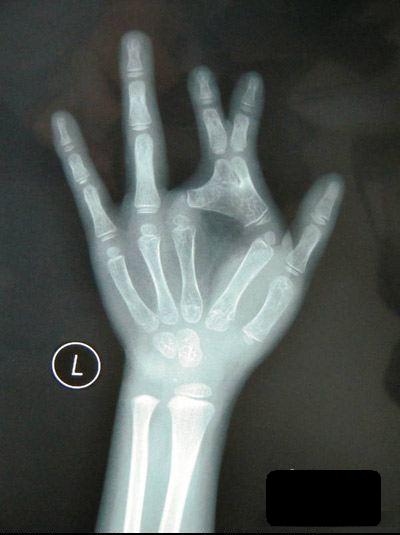

Default Kỳ lạ bé gái có xương tay hình cái kéo

Cô bé có tên Tiểu Na ở Trung Quốc sinh ra đã có xương tay hình cái kéo, nên từ nhỏ em đã không thể chơi trò oẳn tù tì giống như những em nhỏ bình thường khác.

Trò chơi oẳn tù tì vốn là một trò chơi vô cùng đơn giản của các bé, nhưng với Tiểu Na (6 tuổi) người tỉnh Trùng Khánh, Trung Quốc thì đây quả là trò chơi trong mơ, bởi bàn tay em bị dị tật bẩm sinh từ nhỏ với xương bàn tay hình chiếc kéo.

6 năm trước, Tiểu Na ra đời tại một vùng nông thôn của tỉnh Trùng Khánh. Bế con gái trên tay, cha em đã vô cùng kinh ngạc khi thấy trên bàn tay trái của Tiểu Na, đốt ngón cái và ngón trỏ dính liền vào nhau, trông giống hệt một chiếc kéo.

Do hoàn cảnh gia đình khó khăn nên không có tiền chạy chữa, bên cạnh đó tay phải vẫn hoạt động bình thường nên cũng không gây trở ngại lớn cho cuộc sống sinh hoạt của em. Mãi đến năm Tiểu Na 3 tuổi, cha mẹ em mới quyết định đưa em đi khám bệnh, nhưng hầu hết các bệnh viện đều không đảm bảo sẽ chữa trị được cho em.

Mãi đến khi tới bệnh viện Nhi đồng, các bác sỹ mới quyết định tiến hành phẫu thuật thẩm mỹ bàn tay cho Tiểu Na. “Đây là một ca phẫu thuật khó, bởi ngón tay thứ 2 và thứ 3 của cháu đã bị biến dạng giống hình một chiếc kéo, khiến nửa ngón tay còn lại phát triển không bình thường, cái khó nhất là làm thế nào để cấy da lên phần xương ngón tay sau khi được tách ra”, bác sỹ phẫu thuật cho Tiểu Na cho biết.